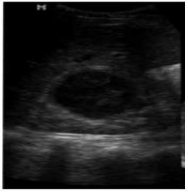

Uma mulher de 17 anos, gestação de 20 semanas, com febre (37,8ºC) foi encaminhada para realização de exame de ultrassonografia renal. O EAS mostrava piúria (20 a 30/campo). A paciente já se encontrava em tratamento com cefalexina, 500 mg VO, três vezes ao dia, que foi mantido por 14 dias. Segue USG realizada:

Corte longitudinal ecográfico do rim direito, mostrando

uma lesão hipecoica bem definida, medindo 48,0mm

Fonte: Vol. 10 • 14ª Edição • março DE 2011 | rbus 21

Qual diagnóstico para paciente atendida: